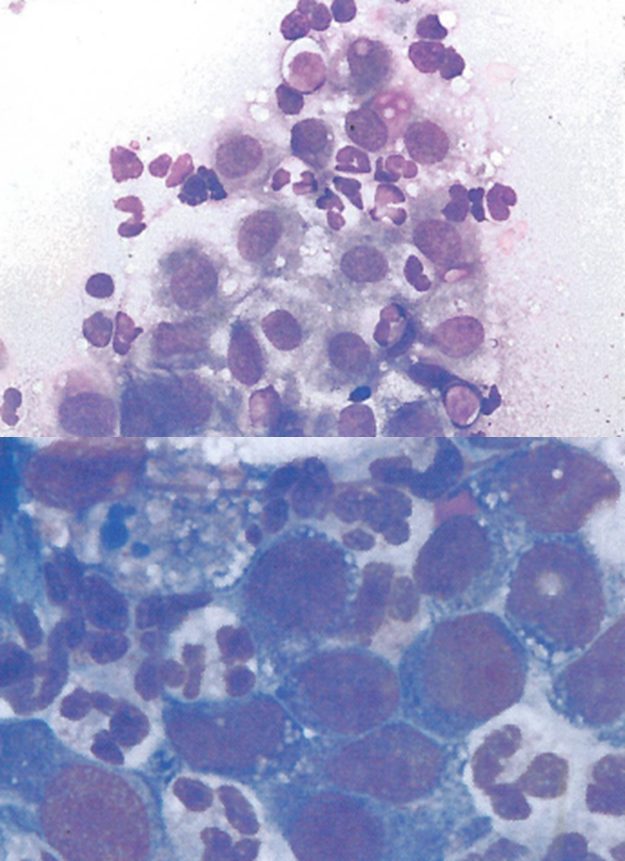

whats this

lymphoma

what are tingible body macrophases

are large phagocytic cells that have numerous

bits of phagocyto's nuclear debris called tingable bodies.

These are also seen in reactive hyperplasia, but more may

be seen in lymphoma.

what are lymphoglandular bodies

are the little blue dots scattered in between cells.

They are burst cytoplasm that then reforms into little blobs

where the phospholipid bilayer has membrane of the outer cell

wall just loops back on itself and makes a little bleb of cytoplasm.